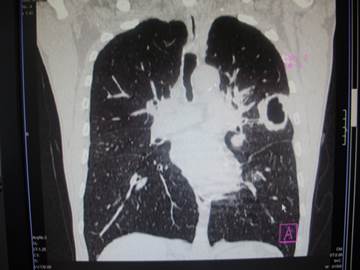

Интерпретируйте данные маммографии. Какие рентгенологические симптомы рака молочной железы выявите?

(рис)

А) сохранение архитектоники

B) наличие кальцинатов

C) вовлечение в процесс соска

D) звездчатый контур, спикулоподобные тяжи

E) четкость контуров

{Правильный ответ}= D